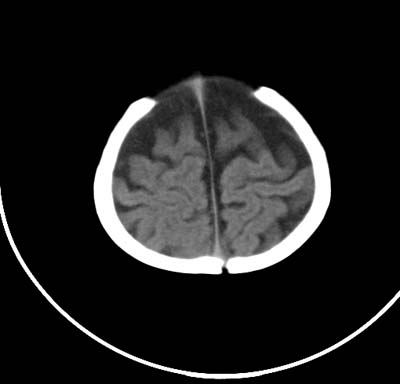

以下是引用影象小泰斗在2008-6-30 15:57:00的发言:[br]双侧额、颞部蛛网膜下腔增宽,纵裂加深, 支持外部性脑积水![br] 双侧基底节点状钙化!

以下是引用jiangjing在2008-6-30 17:19:00的发言:[br]双侧额、颞部蛛网膜下腔增宽,纵裂加深, 支持外部性脑积水![br] 双侧基底节点状钙化![宫内感染形成可能]